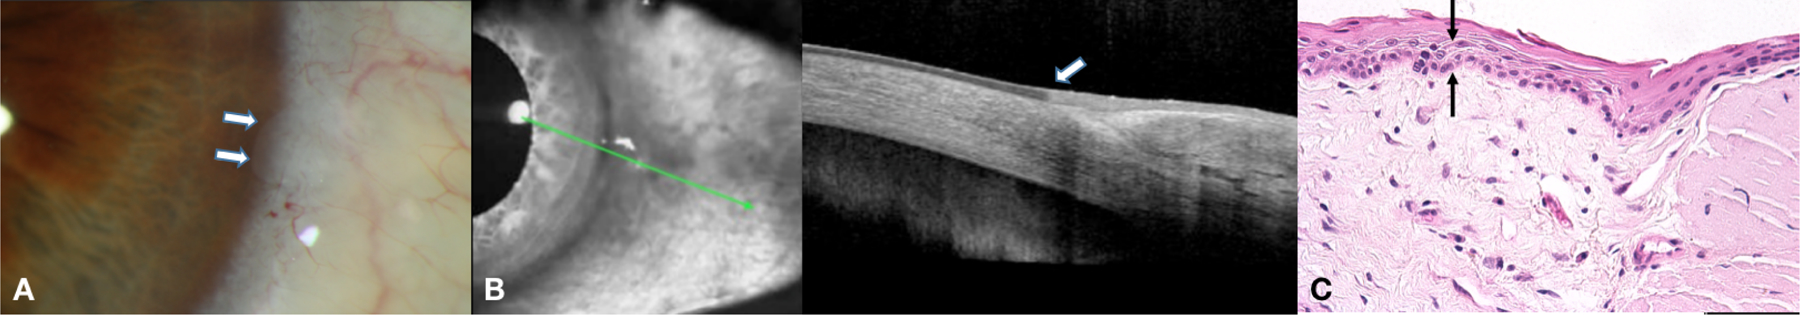

Figure 1.

a. Slit lamp photograph of a 72-year-old black male with a left nasal limbal opacity at 9 o’clock with smooth round borders. b. HR-OCT demonstrating a hyperreflective, thickened epithelium with an abrupt transition between normal and abnormal tissue. c. Examination discloses acanthotic mucosal epithelium with a focus of overlying keratosis (asterisk) and melanosis without atypia present at the basal aspect of the tissue (arrows) (Hematoxylin and eosin, original magnification × 400).

A 72-year-old black male with a 20-pack year smoking history presented for evaluation of a left, opalescent, smooth nasal corneal lesion at 9 o’clock. HR-OCT was characteristic for OSSN with hyperreflective, thickened epithelium (2.2X as compared to normal) and an abrupt transition from normal to abnormal epithelium. He was started on topical interferon alfa-2b (INFα2b). After one month of treatment, no change in the lesion was noted and a biopsy was performed which demonstrated squamous metaplasia of the cornea and melanosis without atypia of the conjunctiva. INFα2b was discontinued and the patient has remained under observation without any changes in his corneal lesion.